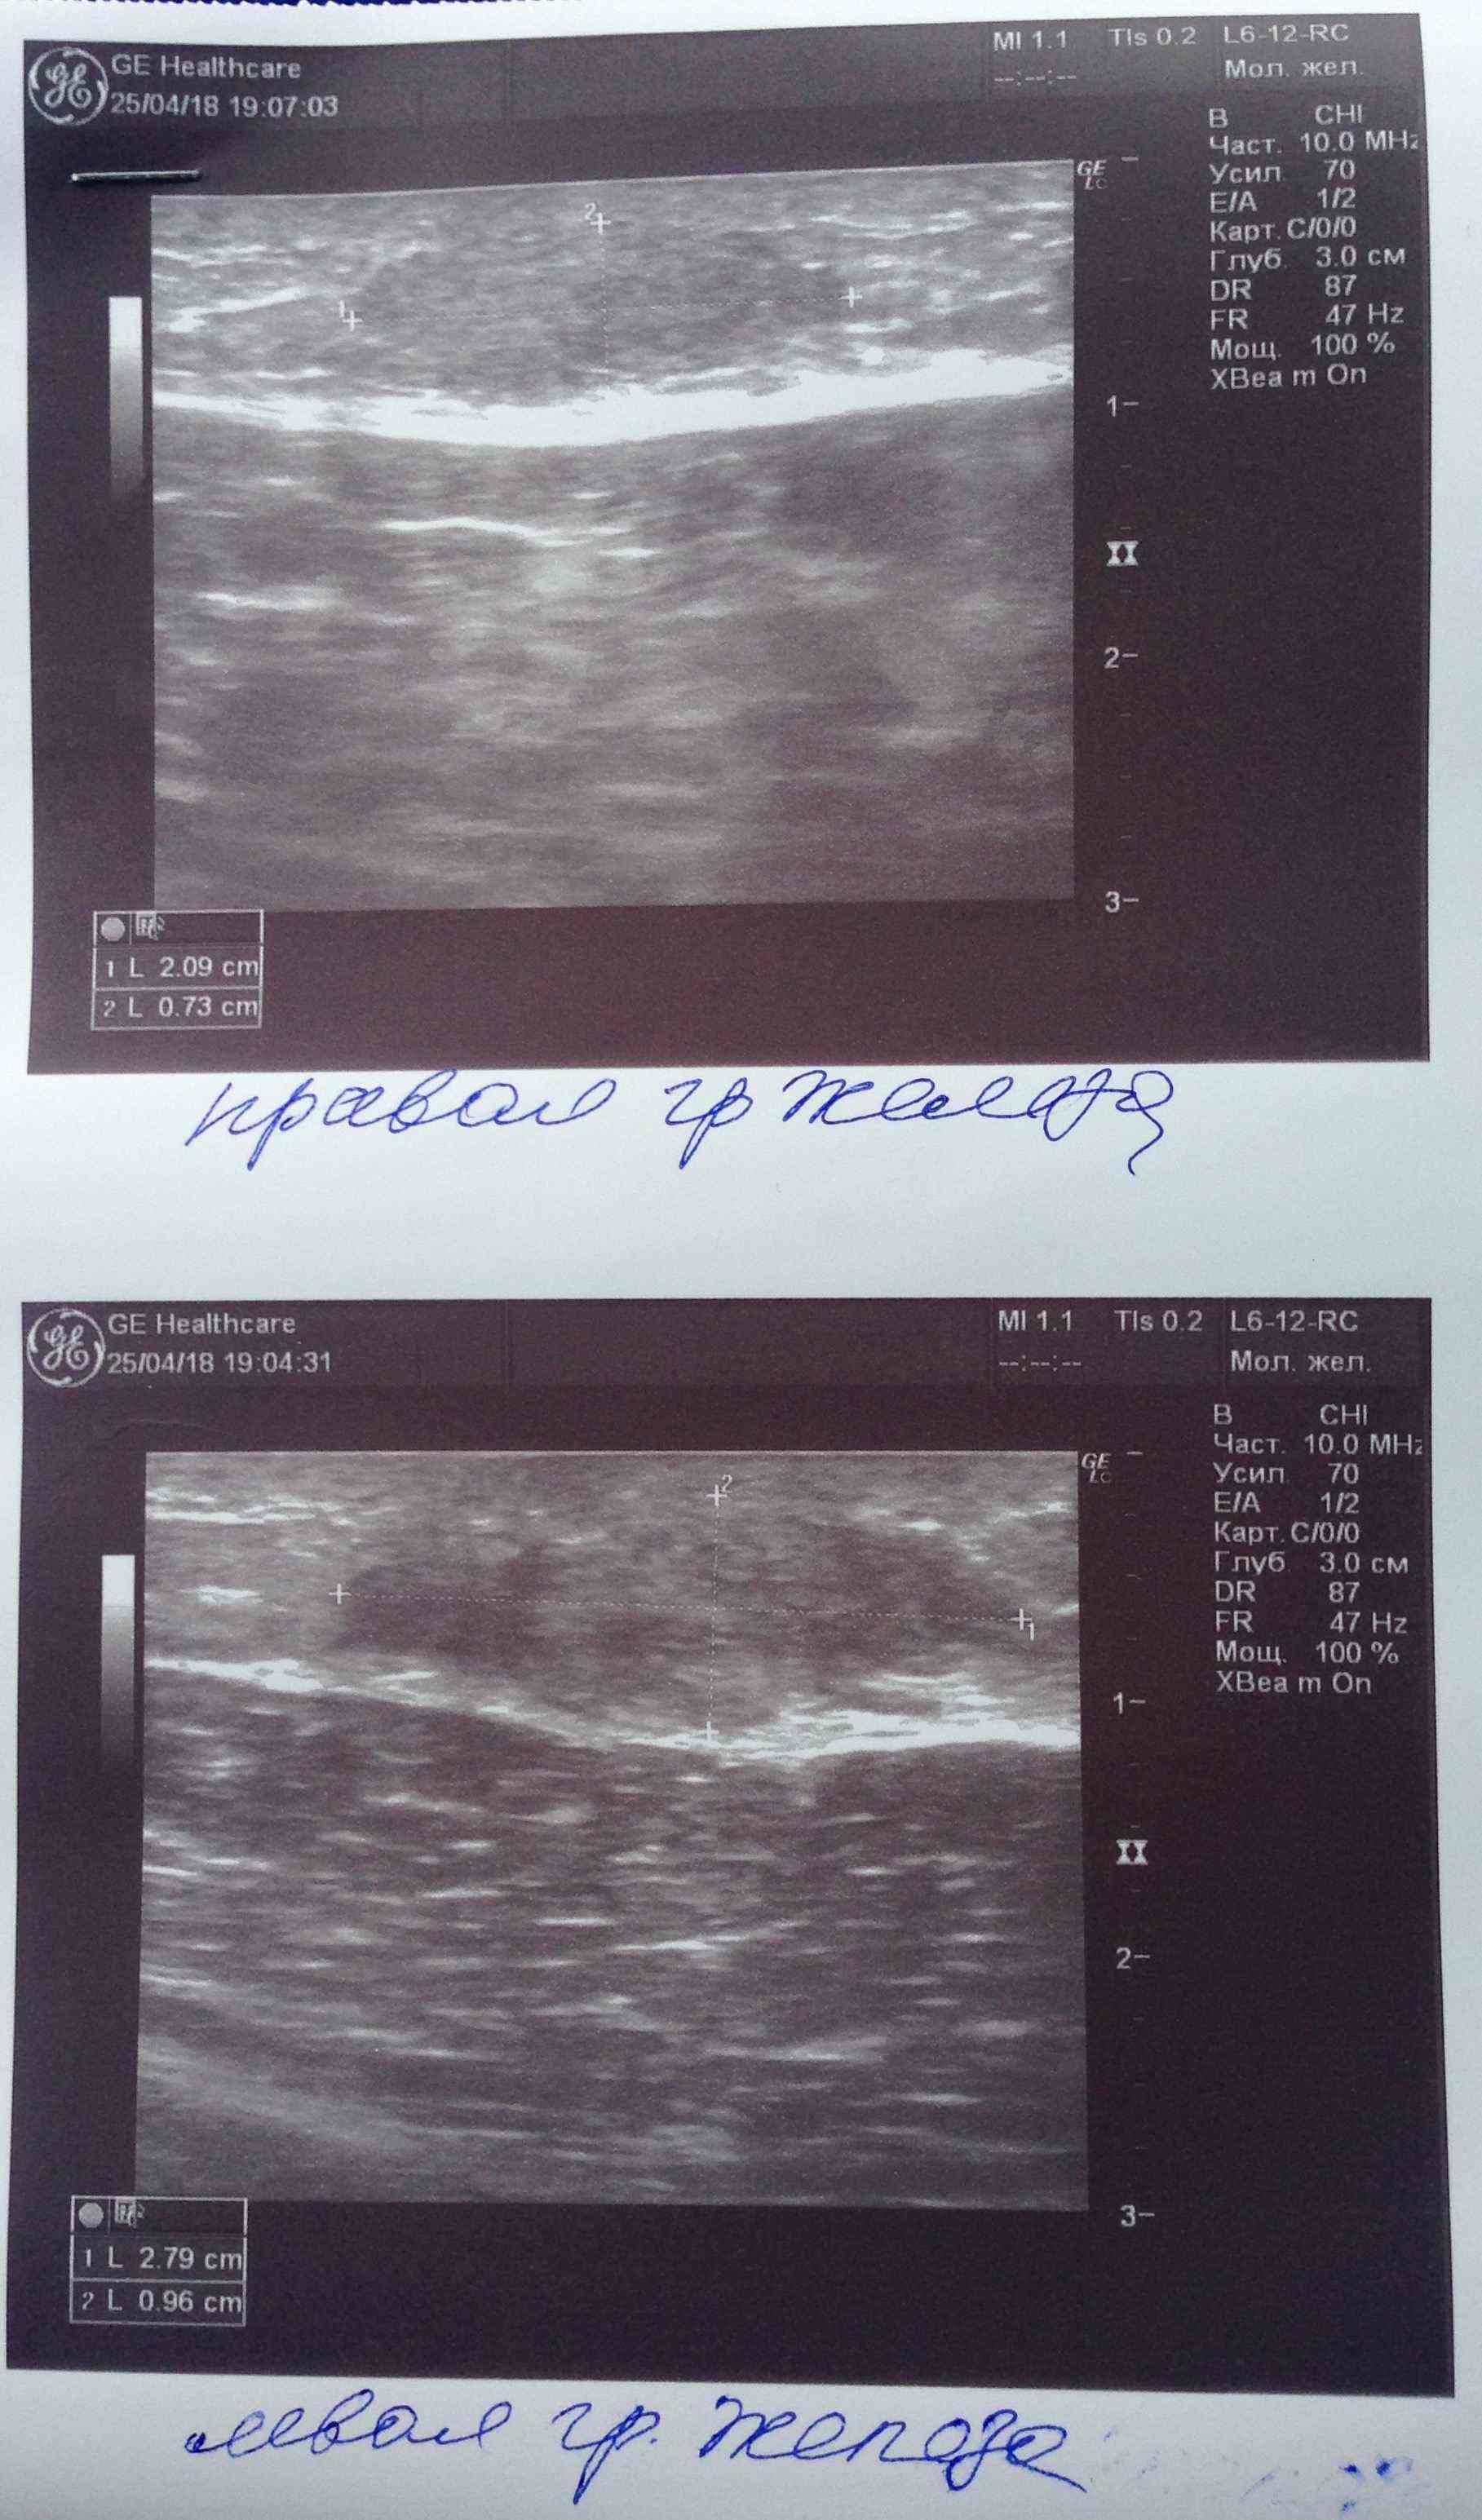

Парни всем доброго вечера! Недавно поднимали вопрос об уплотнении в области сосков на курсах с декой. Суть вопроса что анализы постоянно контролирую как строгая мамка бережет девственность дочки старшеклассницы и они находятся в референсах а уплотнение есть и как будто бы немного растет. Сгонял на УЗИ чтобы расставить все на свои места. В моем случае оно меня порадовало. Думаю что это не единичный случай поэтому и выкладываю инфу сюда. В моем случае гино и не пахло. Имеется небольшое уплотнение состоящее из фиброзно-жировой ткани. Всем здоровья и удачи:swag:

Всем привет. Был курс нанфинил100+проп100. Набухли сиськи. Е2 и пролоктин в норме. PartyKill посоветовал сделать УЗИ .Результат: Эхо-признаки двусторонней геникомастии. Ну врачи привыкли всё драматизировать и слегка преувеличивать. Но лечиться всё равно надо. Посоветуйте братья . До этого проблем с гино небыло.Может эта реакция на нанфинил такая? (Юзал первый раз)Хотя дека прошлым курсом нормально так вкатила.Стаж 4 года, ну разумеется с отдыхом , ПКТ, сдачей анализов. Всё по фэн-шую, всё как мы любим.Сейчас идёт мост , энка250 . Хотелось бы подлечиться а с июня снова в бой )) Выручайте

Посмотреть вложение 14714 Всем привет. Был курс нанфинил100+проп100. Набухли сиськи. Е2 и пролоктин в норме. PartyKill посоветовал сделать УЗИ .Результат: Эхо-признаки двусторонней геникомастии. Ну врачи привыкли всё драматизировать и слегка преувеличивать. Ну лечиться всё равно надо. Посоветуйте братья . До этого проблем с гино небыло.Может эта реакция на нанфинил такая? (Юзал первый раз)Хотя дека прошлым курсом нормально так вкатила.Стаж 4 года, ну разумеется с отдыхом , ПКТ, сдачей анализов. Всё по фэн-шую, всё как мы любим.Сейчас идёт мост , энка250 . Хотелось бы подлечиться а с июня снова в бой )) Выручайте

Ну да, железа увеличина.

Давай тогда сделаем как советовал Дон, фарестон по 60 в день на месяц, после месяца сделать УЗИ повторно и посмотреть на динамику